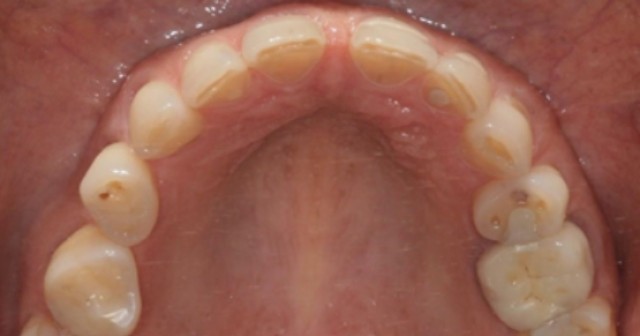

Maxilla Is Key in Comprehensive Treatment Planning

Dr. Jeffrey Rouse builds the case for dentists to keep the maxilla in mind when planning comprehensive treatment.By Jeffrey Rouse

Advanced FGTP: The Inclusion of Airway Prosthodontics

Adding the principles of managing airway issues in patients has helped evolve Facially Generated Treatment Planning for the better.By Jeffrey Rouse